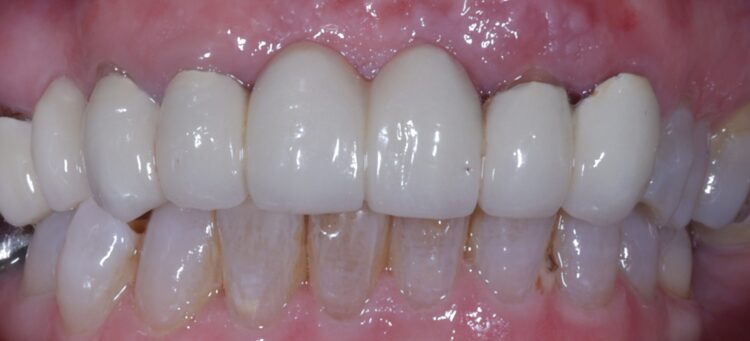

Dr Omar Iqbal replaces a patient’s failing bridge in the aesthetic zone with a new prosthesis fixed in place with two Tapered Pro Conical implants.

A 61-year-old female patient presented with a failing, upper 3-3, metal ceramic bridge, connected to the canines and lateral incisors on either side. The bridge had failed with caries and core fractures on both abutment teeth on the patient’s left side. As such, the patient was keen to repair or replace the bridge without the use of a removable prosthesis at any point during treatment.

The patient returned to the practice for review two weeks post-surgery and to confirm successful and otherwise uneventful healing. Discomfort was minimal and she reported being very satisfied with the outcome. After a healing period of three months, the patient returned to begin making the final prosthesis. Good soft tissue adaptation was noted around the temporary prosthesis and the buccal contour was successfully maintained.